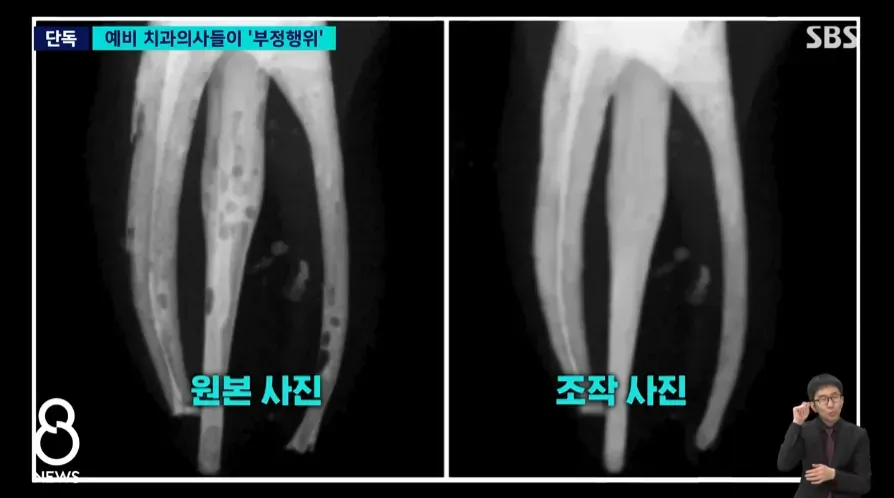

연세대 치과대학 학생들의 실습 사진 조작 부정행위를 보도하는 SBS 뉴스 화면

예비 치과의사들의 부정행위를 보여주는 원본과 조작 사진 비교 이미지